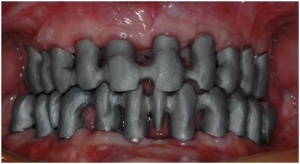

-la réalisation des bridges provisoires